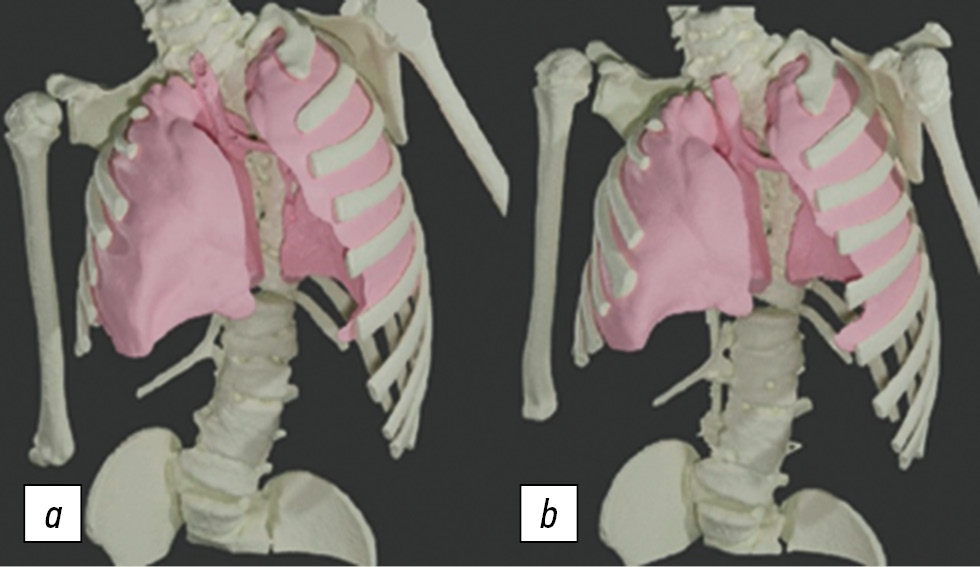

According to the analysis of CT volumetry (Fig. 4), the median total lung tissue volume before surgery was 860.6 cm3 (IQR 415.2) cm3. After the surgery, the median total lung volume reached 951.3 (IQR 441.3) cm3. After 6 months, the lung volume on the side of costal synostosis increased by 13% and that on the contralateral side by 4%. Thus, the lung volume tended to increase to a greater extent on the side of the costal synostosis, but it did not reach a statistically significant level. The p-values for the lung volume values were 0.204973 on the synostotic side and 0.35883 on the contralateral side.

Fig. 4. CT volumetry. Patient, 6 years old: a, the lungs before the surgery; b, appearance 6 months after the surgery: a change in the spatial position of the shoulder girdle, an increase in the hemithoracic volume on the concave side, and an increase in the right lung by 72.8 cm3 (22.6%) and the left lung by 62.3 cm3 (20.7%). The total lung volume 6 months after the surgery increased by 21.7% (135.1 cm3)

According to the correlation analysis of lung volumes on the side of the costal synostosis and the contralateral side before the surgery, the p-value was 0.880099, whereas according to the analysis of volumes after the surgery, it was 0.925588, which indicates a high dependence of volumes. The lung volume on the concave side is always less than that on the convex side. The increase in the lung size after the surgery occurred approximately equally (Fig. 5).

Volumetry using multislice computed tomography can supplement the diagnostic map in the preoperative period and at stages of surgery. However, the results of the analysis of preoperative treatment data and at its stages revealed no significant difference in the indicators. Moreover, a relationship was established between lung volumes on the side of costal synostosis and healthy side both before and after the surgery. Before the surgery, the lung volume on the concave side was less than that on the convex one, taking into account the physiological difference in size between the right and left lungs. The lung size after the surgery on the convex and concave sides increased in approximately equal extent.